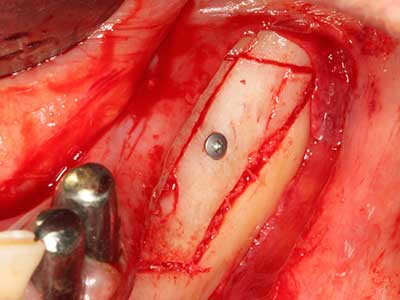

Indication: Preparation near nerves

Indication: Apical resection

When surgical procedures are performed on bone in the immediate vicinity of sensitive structures such as blood vessels or nerves, rotary instruments pose a significant risk of iatrogenic injury. Piezoelectric devices can be helpful for preparation of bone covers and removal of hard tissue close to nerves, particularly for exposure of nerves after iatrogenic injury but also during nerve lateralization for resective and reconstructive procedures or implant placement (Fig. 17-20). Light contact between the piezotip and the nerve does not generally result in damage but proceeding incautiously with saw-like motions or attachments where a residual bone substrate remains may cause temporary or even permanent nerve damage. However, the risk of damage is considered to be substantially lower than when using saws or milling instruments (Pereira, Gealh et al. 2014).